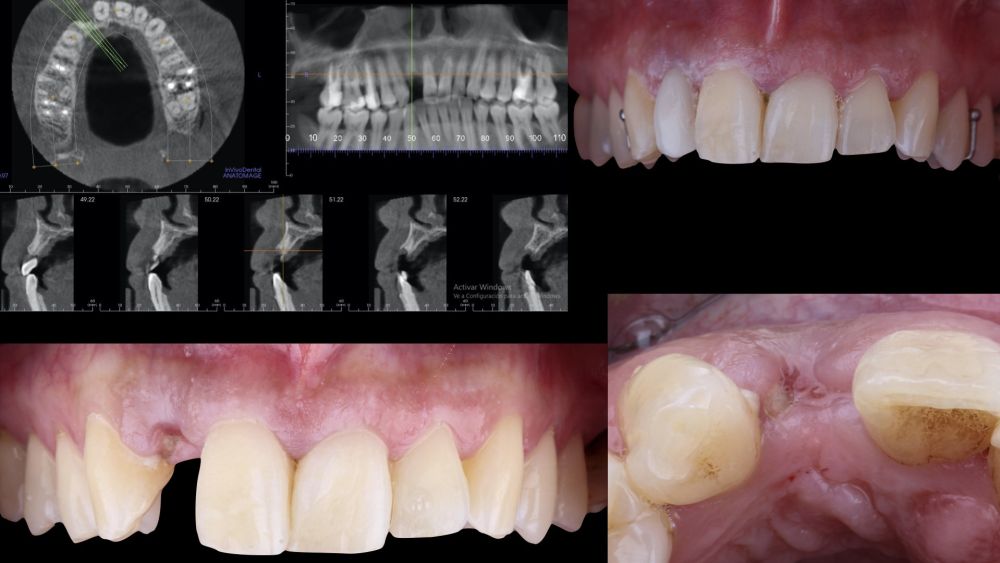

1.1 Diagnosis and Treatment Plan

A 29-year-old female patient presented to our dental clinic following trauma to the right maxillary lateral incisor (1.2). The trauma resulted in a fracture of the entire anatomical crown; consequently, only a root remnant in a subgingival position remained. The root remnant was diagnosed as non-restorable, and the available therapeutic options were thoroughly discussed with the patient. It was decided to replace tooth 1.2 with a dental implant, and the following treatment plan and clinical sequence were established: Phase I: extraction of the root remnant 1.2 and reconstruction of the alveolar process using a minimally invasive alveolar preservation procedure.

1.2 Treatment

• Phase I: atraumatic extraction of the root remnant 1.2 was performed, followed by curettage of the granulation tissue. Subsequently, the alveolus was filled with an inorganic bovine bone graft (0.25–1mm) combined with autologous platelet- and leukocyte-rich fibrin. Finally, the edges were approximated and sutured with four simple stitches from the vestibular mucosal margin to the palatal aspect. Subsequently, the patient continued using her removable partial denture as a provisional restoration (Figure 1).

* Phase II: healing proceeded without complications. After 5 months from the alveolar preservation surgery, guided implant surgery was planned at position 1.2 (Figure 2). For this purpose, a DICOM file from cone beam computed tomography (CBCT) and an STL file obtained from scanning with an intraoral optical scanner were used. Using this information, a dental support surgical guide was fabricated (Figure 3). The surgical guide was anchored onto the teeth and guided the preparation of the implant bed and the placement of the implant. The guided surgery technique consisted of flap surgery, preparing and inserting the implant (3.5 x 11.5 mm) according to the standardised Nobel Active® guided surgery protocol (Nobel Biocare AB, Gothenburg, Sweden). Once implant 1.2 was placed,a gingival graft composed of epithelium and connective tissue from the palatal masticatory mucosa was obtained. Subsequently, the superficial epithelial layer of this graft was deepithelialised extraorally using a 15C scalpel blade in order to obtain a connective tissue graft from the underlying layer18.